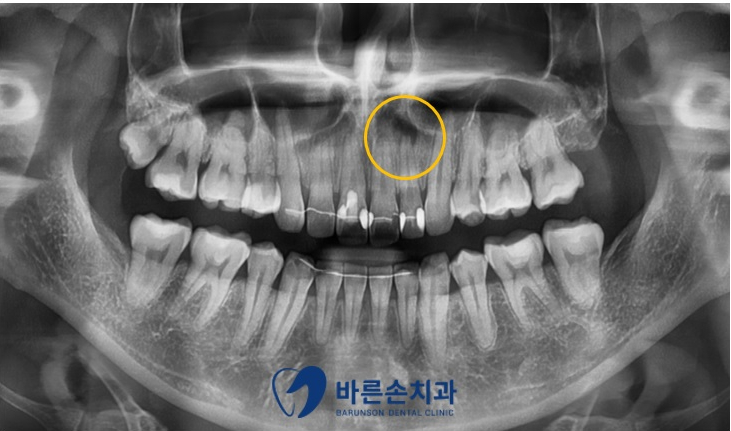

정확한 진단을 위해 육안 상의 검진만이 아닌

파노라마 촬영을 진행하여 치아와 치조골 등 전체적인 상태를 확인해 보았습니다

파노라마 촬영 결과 앞니 특정 부위에 염증으로 의심되는 구조물이 보여

좀 더 정확한 확인을 위해 특정 부위에 치근단 촬영을 추가로 진행하였습니다